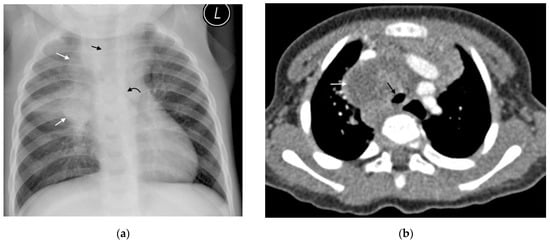

Figure 8. (a,b): (a) Supine AP chest radiograph in a 17-month-old male with PTB demonstrating right sided pleural effusion with veiling of the right hemi-thorax and a lamellar component tracking up along the lateral chest wall (curved white arrows). There is also attenuation of the bronchi bilaterally (straight black arrows), bowing of the trachea from lymphadenopathy (curved black arrow) and an enlarged, globular-shaped heart, consistent with a pericardial effusion (confirmed on ultrasound, not shown here). (b) Chest ultrasound confirming the pleural effusion (star) seen as hypoechoic fluid between the parietal pleura, diaphragm, and right lung.

Pleural disease occurs via either of two mechanisms: direct spread from a caseating sub-pleural focus (consolidation or lymph node) or via hematogenous spread [1]. Pleural disease is more common in older children [2]. A pleural effusion may occur secondary to an obstruction of lymphatic drainage or as a result of a hypersensitivity reaction. This explains why most pleural fluid cultures are negative [1]. They are typically unilateral, lamellar (a linear density extending along the lateral chest wall and sparing the costophrenic angle), and associated with consolidation or lymphadenopathy [3,6] (Figure 8). A large volume of pleural fluid needs to collect before becoming visible on plain films [2].

A simple pleural effusion on ultrasound is characterized by an anechoic fluid collection separating the visceral and parietal pleura. Ultrasound has been shown to be more sensitive than a chest radiograph for the presence of a tuberculous pleural effusion [10]. An added benefit of ultrasound is the ability to further characterize the effusion by detecting the presence of loculations or empyema as well as guide drainage of these effusions if needed.